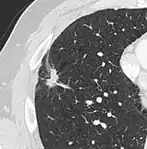

Low attenuating nodule (in this case a fat containing hamartoma).[9]

Cavitation with relatively thick wall, in this case aspergilloma).[9]